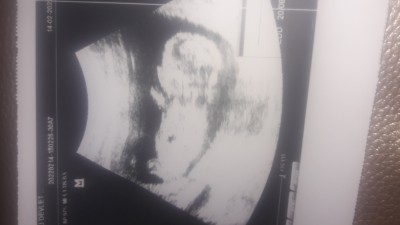

Sizce cinsiyeti ne olabilir.Tahmin yapabilirmisiniz.

Gebelik haftası 13+4